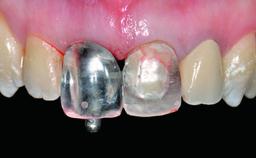

| Abutment Type | CAD/CAM |

| Prosthesis Type | FDP |

| Loading Protocol | Conventional or early |

| Retention | Screw-retained Screw-retained |